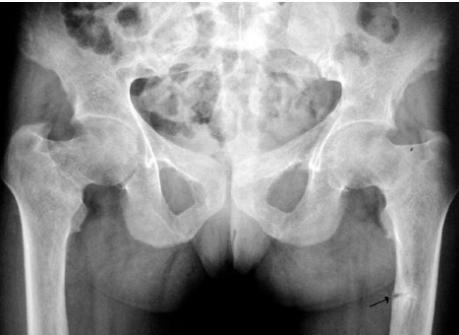

- Trefoil pelvis – acetabular protrusion

- Neck of femur

- Pubic bones